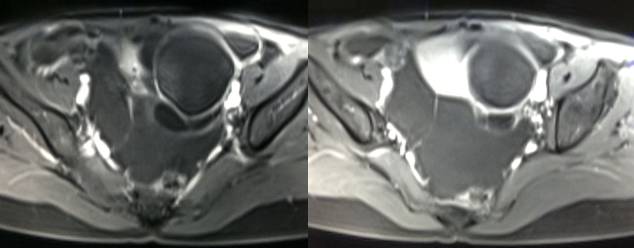

黄体血肿早期:囊内出血较多时,表现为卵巢内近圆形囊肿,囊壁厚,内壁粗糙。

黄体血肿中期:黄体血肿内血液凝固,部分吸收,囊壁变薄而,内壁光滑。

黄体血肿晚期:血液吸收后囊肿变小,转变为白体,内部回声呈实性稍高回

声,与周围卵巢组织分界不清,面靠彩超显示其周围环状血流判断,当血液完全吸收后形成黄体囊肿,囊壁变得光滑,与卵巢其他囊肿难以区分。

根据时间不同MR信号也有所不同,TIWI脂肪抑制序列可以鉴别脂肪和出血。

卵巢囊肿:呈均匀的T1WI 低信号,T2WI 高信号,边界清楚,壁薄,大多数病灶直径≤5 cm,但囊肿的起源及定性诊断困难。

巧克力囊肿:常呈多发的单囊或多囊改变,病灶大小不等,囊壁厚薄不均,囊内信号复杂,囊内或各囊腔间血液因出血时期不同,信号常呈多样性,囊肿内反复出血、破裂,形成相互粘连的多房性囊肿,是其较为特征性的表现。

在鉴别卵巢畸胎瘤、出血性囊肿或巧克力囊肿时,MR 脂肪抑制T1WI 可明确肿块内高信号成分是脂肪还是出血,同时由于脂肪组织与非脂肪组织的共振频率不同,在两者交界处沿磁场频率编码方向出现化学位移伪影,但出血性囊肿与巧克力囊肿的鉴别有时较为困难。